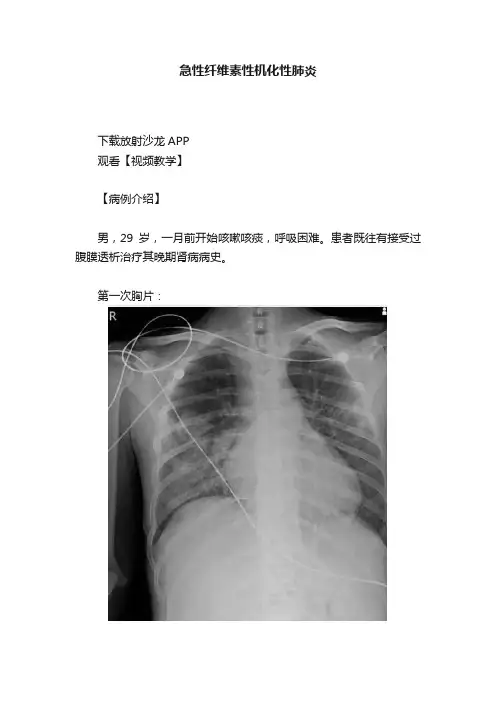

急性纤维素性机化性肺炎下载放射沙龙APP观看【视频教学】【病例介绍】男,29岁,一月前开始咳嗽咳痰,呼吸困难。

患者既往有接受过腹膜透析治疗其晚期肾病病史。

第一次胸片:第一次CT:两周后CT:高剂量类固醇治疗三周后:(第一次胸片示两肺中野及右肺下野多发斑片状高密度影。

胸部CT示多发斑片状磨玻璃样密度增高影以及实变影,同时伴有小叶间隔的增厚。

其中有些病灶部分表现为“铺路石征”。

两周后CT随访显示这些病灶的密度和范围都增大。

电视辅助胸腔镜肺活检下,活检标本病理诊断结果为急性纤维素性机化性肺炎。

上述病变经高剂量糖皮质激素治疗三周后明显改善。